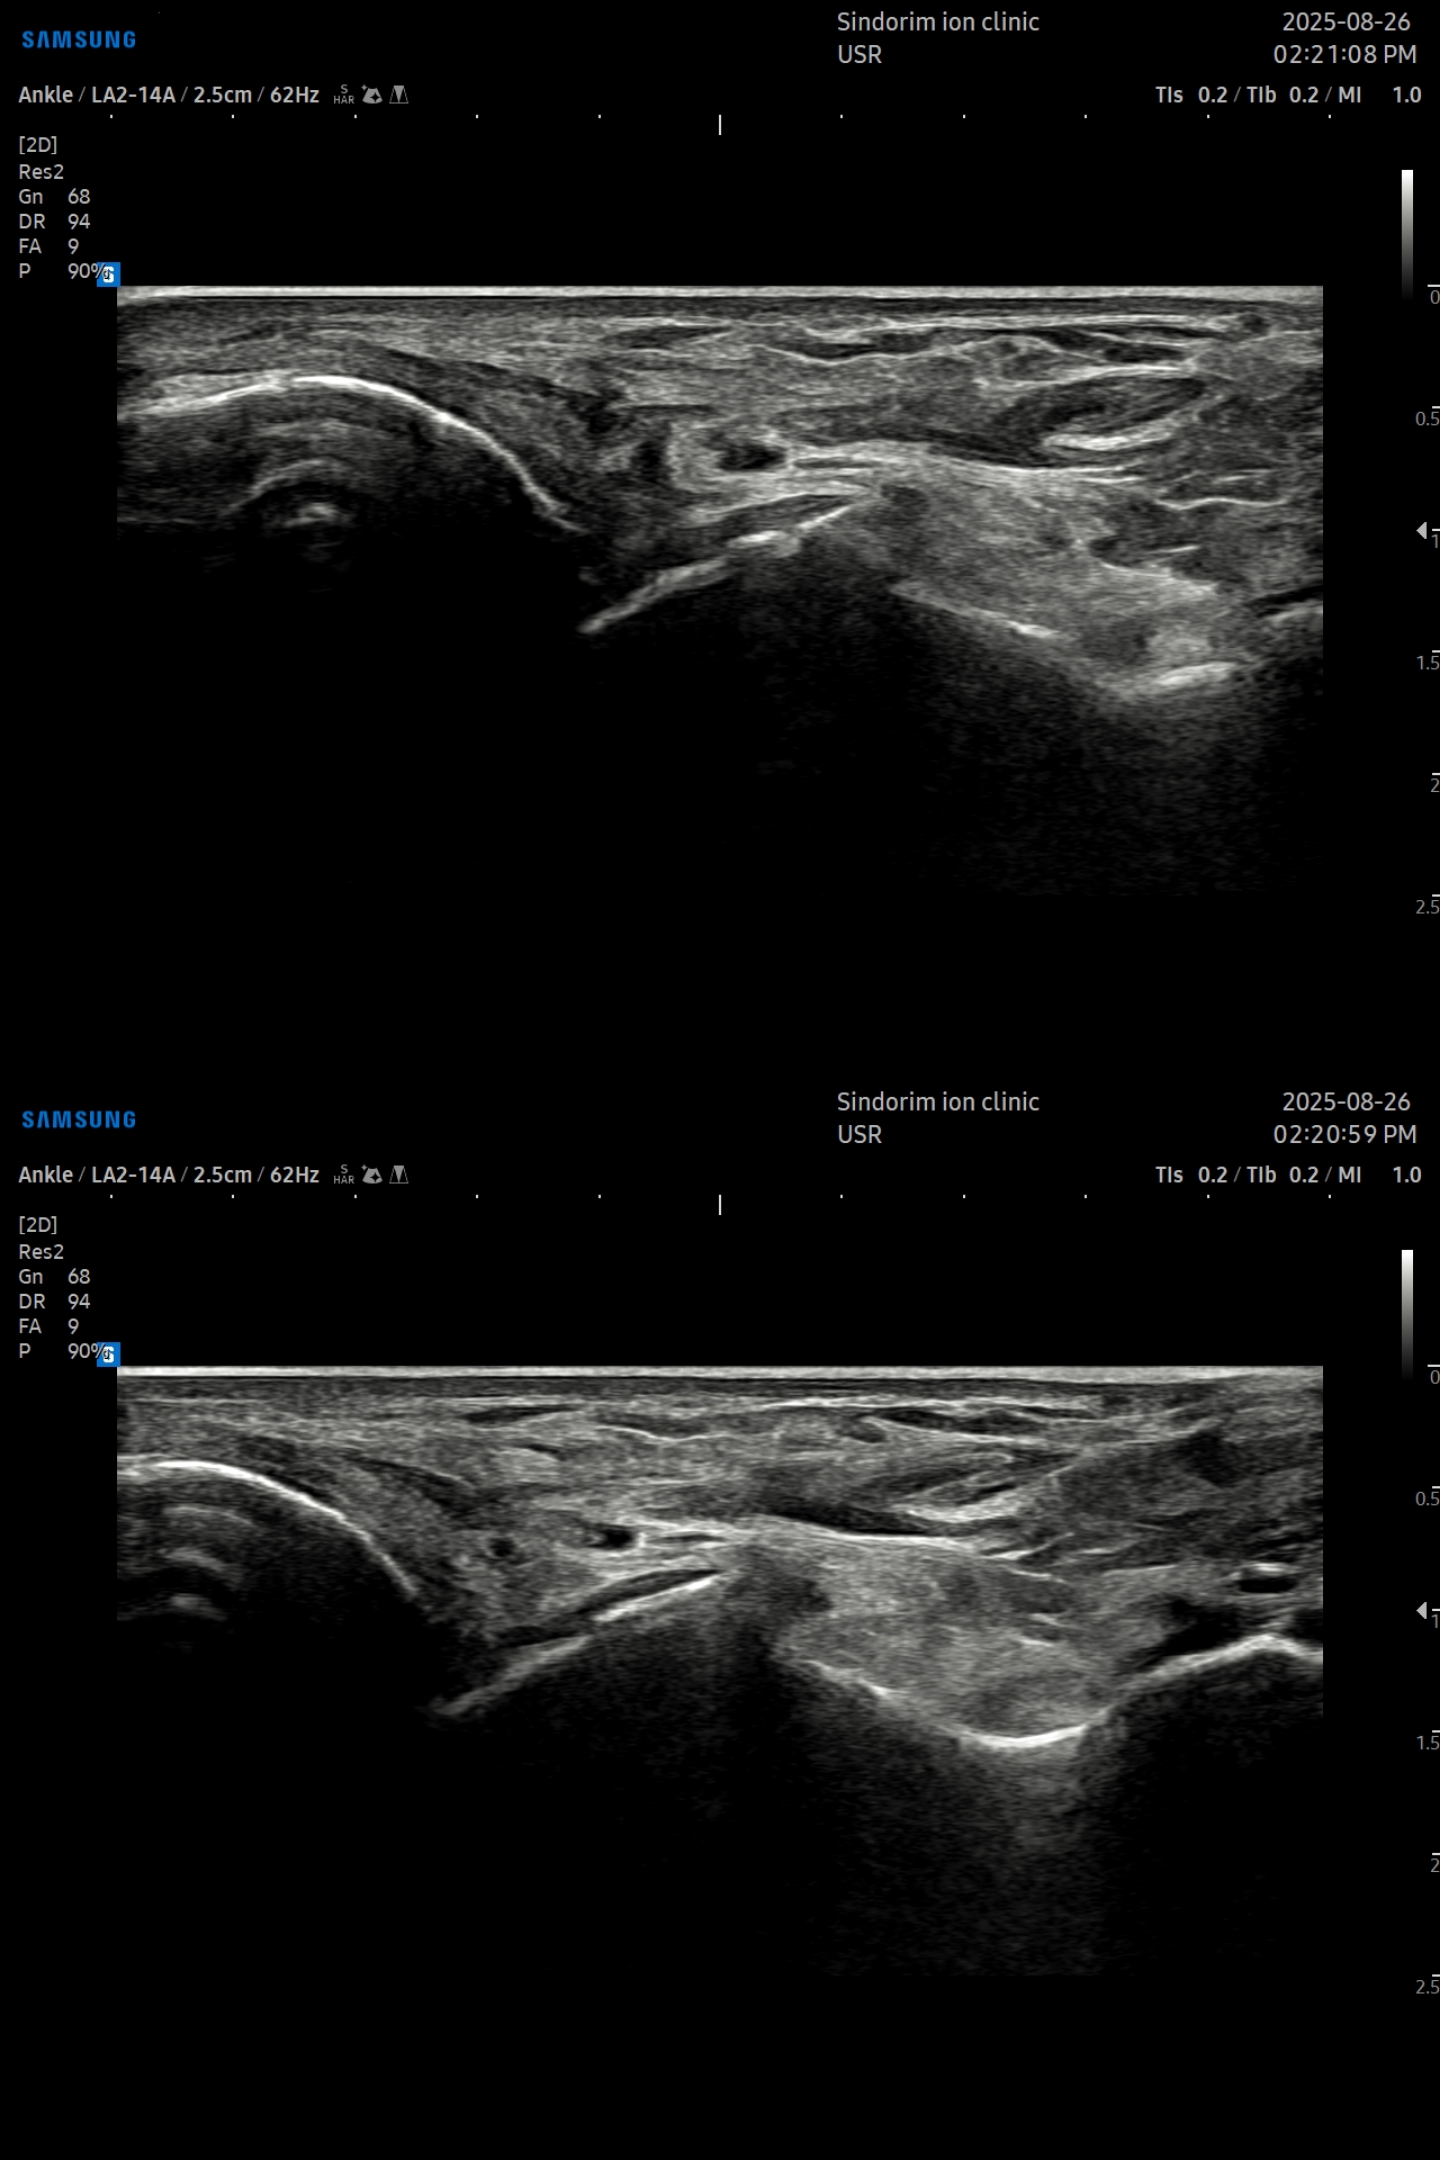

- 치료기간 : 25 . 5 . 3 ~ 25 . 9 . 11

- 치료횟수 : 10 회 (2 cycle)

우측 발 (치료 전 → 후)